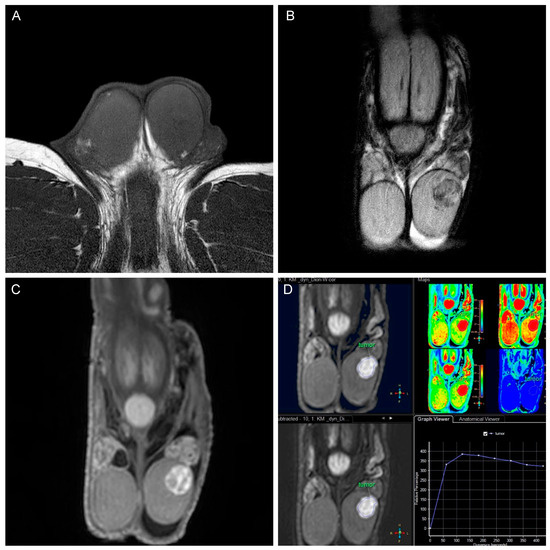

3.2. Results of MRI

3.2.1. Tumor Signaling in Relation to Contrast Agent

3.2.2. Diffusion Restriction

3.2.3. Morphological Characteristics of the Tumors